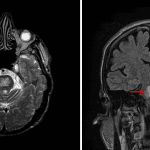

- T2/FLAIR signal hyperintensity and restricted diffusion in the central pons with peripheral sparing and no associated mass effect

- No associated enhancement

- No evidence of acute hemorrhage or hydrocephalus

- Osmotic demyelination

T2/FLAIR signal hyperintensity and restricted diffusion in the central pons without associated mass effect or enhancement, which is primarily concerning for osmotic demyelination (central pontine myelinolysis). Recommend correlation with serum sodium measurements.